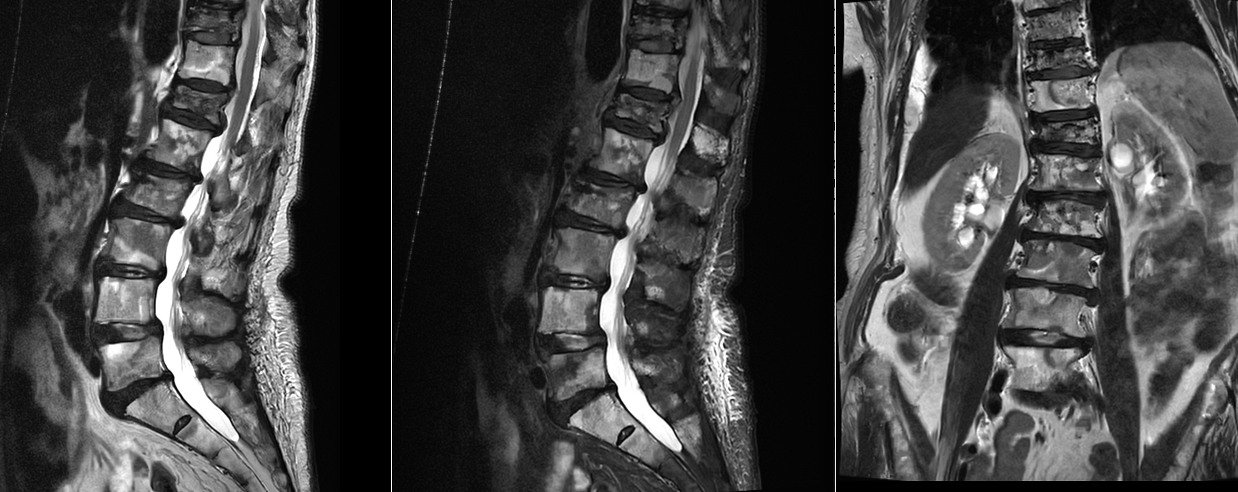

Tumorile secundare, cunoscute sub numele de metastaze vertebrale, sunt de departe cele mai frecvente. Coloana vertebrală este unul dintre cele mai comune locuri de metastazare deoarece este bogat vascularizată. La mulți pacienți oncologici, vertebrele devin un „teren” de implantare pentru celulele tumorale provenite din alte organe.

Metastazele la nivelul coloanei vertebrale apar frecvent în cancerele de sân, plămân, prostată, rinichi sau tiroidă. Acestea pot fi singura manifestare a bolii oncologice sau pot apărea într-un stadiu avansat al bolii.

Diagnosticul tumorilor spinale osoase se bazează pe imagistică de înaltă performanță. Rezonanța magnetică este investigația principală, deoarece oferă informații detaliate despre os, măduvă și nervi. Tomografia computerizată este utilă pentru evaluarea distrugerii osoase.